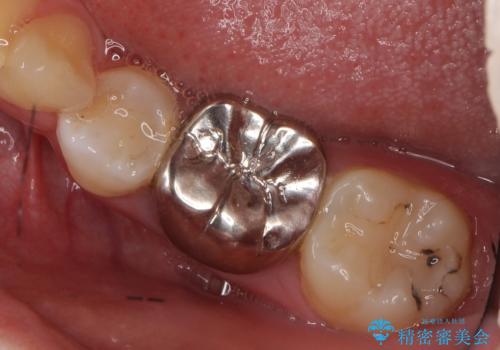

- 左下の銀歯の状態が悪く抜歯してブリッジにした患者様です。

- 36.3万円 (ジルコニアクラウン 10万円×3、仮歯1万円×3)費用は治療当時の料金となります

途中全体矯正をはさみ、根の向きが並行になった状態でブリッジを入れることができました。